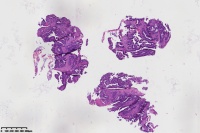

中分化腺癌?

性别

女

年龄

67岁

临床诊断

一般病史

直肠占位

标本名称

大体所见

腺癌(低一中 分化)

中分化腺癌